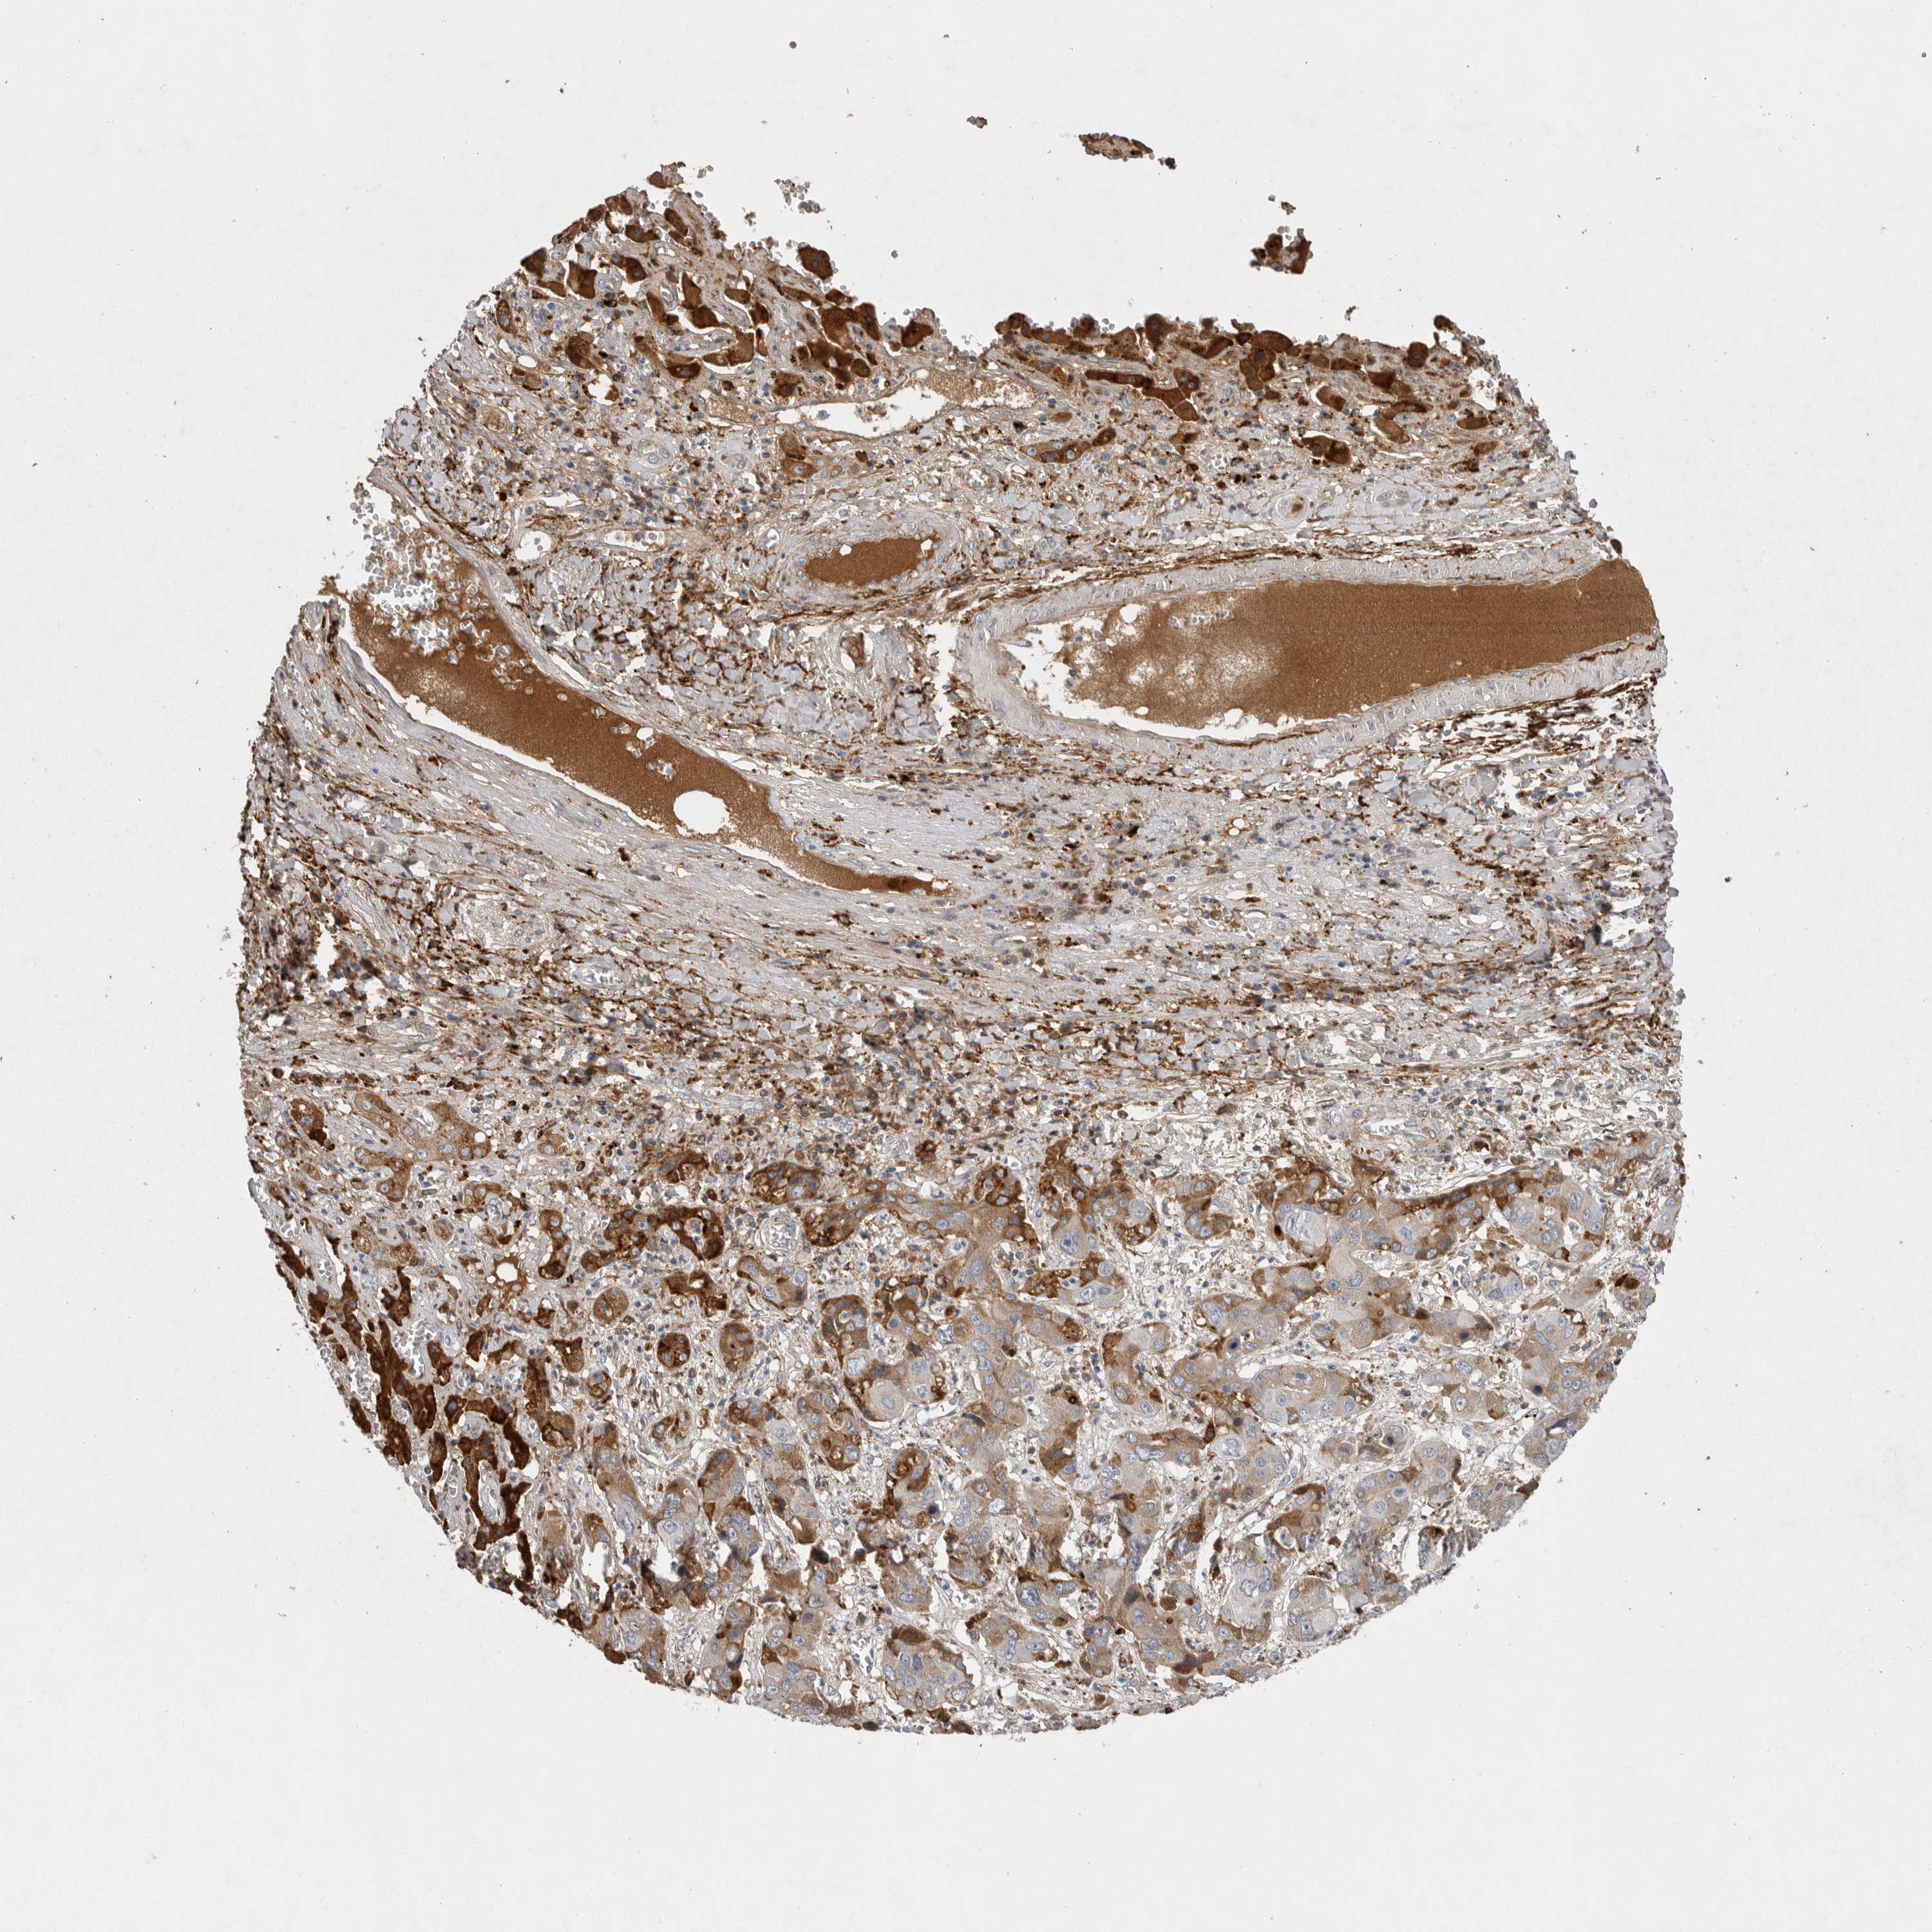

LIVER CANCER - Protein expressioni

A mouse-over function shows sample information and annotation data. Click on an image to view it in a full screen mode. Samples can be filtered based on level of antibody staining by selecting one or several of the following categories: high, medium, low and not detected. The assay and annotation is described here.

Note that samples used for immunohistochemistry by the Human Protein Atlas do not correspond to samples in the TCGA dataset.

Antibody stainingi

Antibody staining in the annotated cell types in the current human tissue is reported as not detected, low, medium, or high, based on conventional immunohistochemistry profiling in selected tissues. This score is based on the combination of the staining intensity and fraction of stained cells.

Each image is clickable and will lead to virtual microscopy that enables deeper exploration of all samples and also displays staining intensity scores, fraction scores and subcellular localization as well as patient and tissue information for each sample.

Antibody HPA027367

Antibody HPA027396

Antibody CAB005036

Staining

High

Medium

Low

Not detected

Intensity

Strong

Moderate

Weak

Negative

Quantity

>75%

75%-25%

<25%

None

Location

Nuclear

Cytoplasmic/membranous

Cytoplasmic/membranous,nuclear

Cholangiocarcinoma

Carcinoma, Hepatocellular, NOS